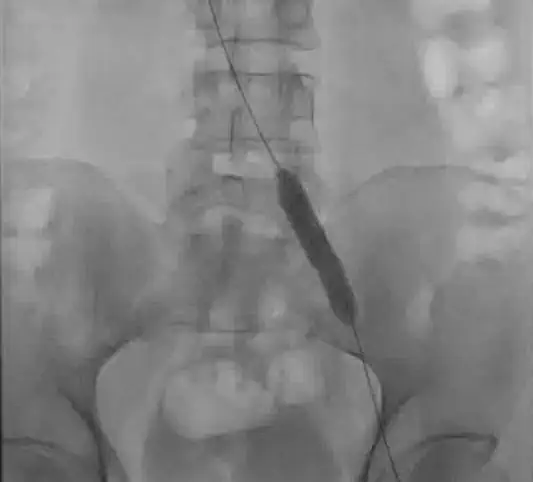

To treat the compression, first, you need to prove that it is there. While venography can show compression, the gold-standard is intravascular ultrasound (IVUS). IVUS can show the compression and prove that the artery is compressing the vein. Some patient will have a different reason for compression. For instance, a tumor. So confirming the reason for the compression is important.

Next, the compression is fixed with a balloon (venoplasty). Often, a stent is placed to keep the vein open.